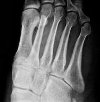

Рентгенография стопы. Рентгенографическое исследование проводят для оценки состояния дистальной линии костей предплюсны, плюсневых костей и суставов стоп, образованных этими костями. В травматологии методика применяется при переломах и переломах. В ортопедии процедура применяется при плоскостопии, изогнутой стопе, других врожденных и приобретенных деформациях стопы, дегенеративно-дистрофических заболеваниях. В онкологии метод назначают при опухолях костей стопы и в гнойной хирургии, если есть подозрение на распространение гнойных процессов в костной ткани. Стандартный поиск выполняется в двух (прямой и наклонный или прямой и боковой) или в трех проекциях (прямой, наклонный и боковой).

Основным показанием для рентгенографии стопы в травматологии являются переломы плюсневой кости. Редко, метод используется в диагностическом поиске с менее частыми переломами костей предплюсны и переломами костей стопы. В ортопедии назначают диагностическую процедуру для косолапости, плоскостопия, вальгусной деформации, других приобретенных и врожденных пороков развития. В области онкологии и гнойной хирургии исследование показано при подозрении на опухоли, поражения костей стопы с глубокими формами криминала, абсцессы стопы и другие гнойные процессы.